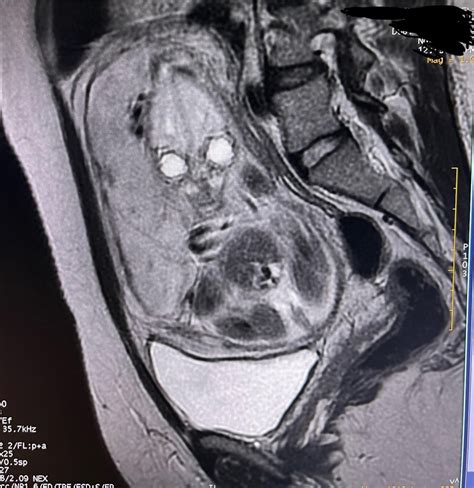

• Magnetic Resonance Imaging (MRI): Uses magnetic fields and radio waves to create detailed images. MRI is generally safe during pregnancy, but certain types of MRI contrast agents should be avoided.

Before considering a CT scan while pregnant, healthcare providers often explore alternative imaging methods that do not involve ionizing radiation. These include:

• Ultrasound: Uses sound waves to create images and is generally considered safe during pregnancy.

If these alternatives are not sufficient, the healthcare provider may proceed with a CT scan, taking precautions to minimize radiation exposure.